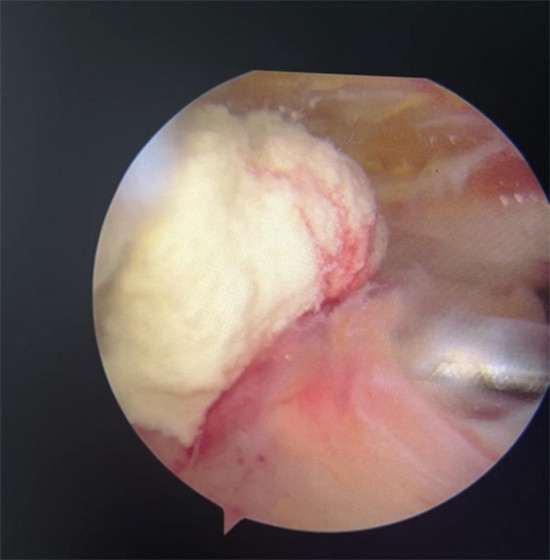

賀大媽慕名來(lái)廣安醫(yī)院找羅軍主任就診,面對(duì)羅醫(yī)生,賀大媽哭訴:“羅醫(yī)生,我真想剁下自己的這只胳膊。”羅軍主任根據(jù)患者的癥狀拍片,診斷為岡上肌鈣化性肌腱炎,隨后,羅醫(yī)生為李大媽進(jìn)行了肩關(guān)節(jié)鏡微創(chuàng)手術(shù),竟從她的右肩“擠”出“牙膏”。

羅軍主任表示,很多人會(huì)把肩痛都?xì)w因于肩周炎,這是一個(gè)很大的誤區(qū)。其實(shí),肩痛人群中只有15%左右是肩周炎,大部分肩膀疼痛由于肩袖損傷、肩峰撞擊征、鈣化性肌腱炎。而大多數(shù)人也因此認(rèn)為忍一忍就會(huì)自愈,常常延誤治療,關(guān)節(jié)鏡微創(chuàng)治療鈣化性肌腱炎,可以快速緩解疼痛,同時(shí)可以修復(fù)肩袖損傷,清理肩膀骨刺。